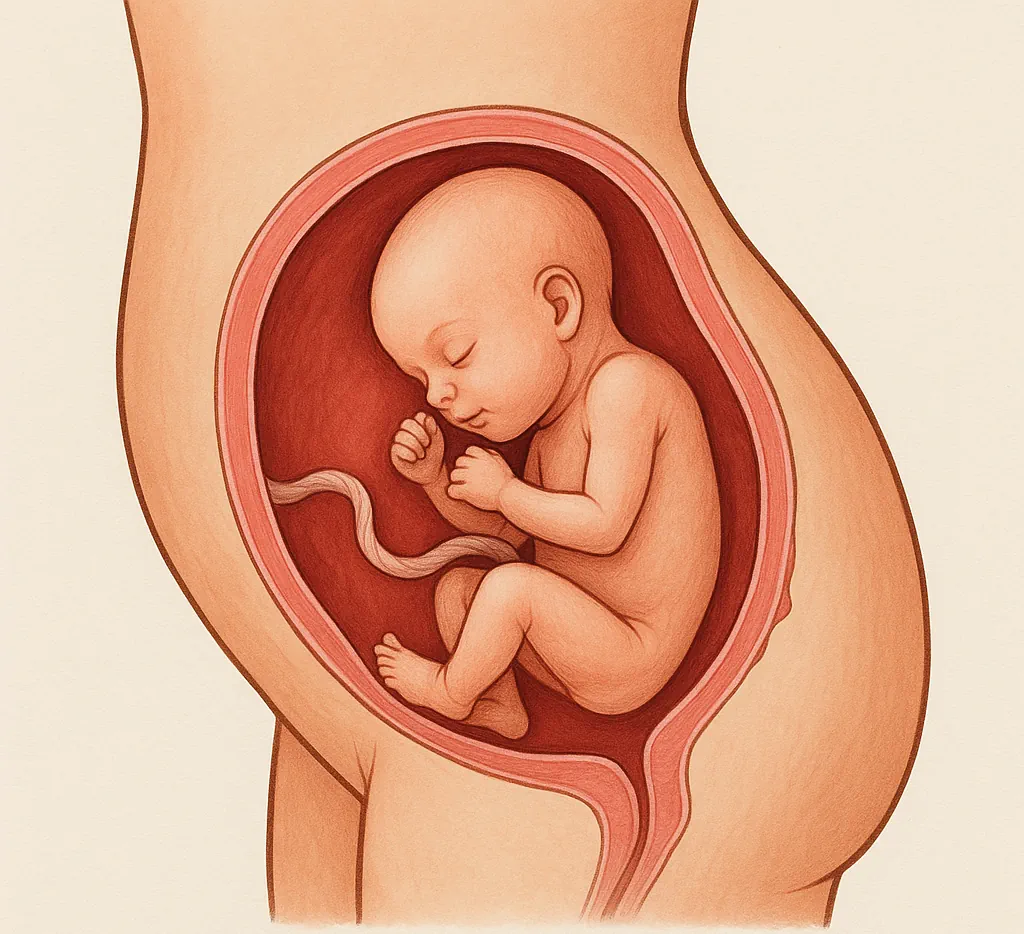

What Happens in the 17th Week of Pregnancy?

At 17 weeks pregnant, your baby is growing rapidly and your body is going through beautiful, visible changes.

Inside your womb, your little one is forming a protective layer called vernix caseosa — a creamy coating that protects their delicate skin from the amniotic fluid.

Meanwhile, your uterus is expanding, your belly is becoming rounder, and your breasts may feel larger or more sensitive as your body prepares for breastfeeding.

Baby Development in Week 17 of Pregnancy

Your baby is now about 12.5 cm long (roughly the size of a pen) and becoming more active every day.

They can now move their hands and legs, touch their face, and even suck their thumb — practicing essential reflexes for life after birth.

Baby’s Appearance

At this stage, your baby looks slender and delicate, slightly longer than the palm of your hand.

Their body hasn’t yet stored much fat, but in the coming weeks, a layer of body fat will form to help regulate temperature after birth.